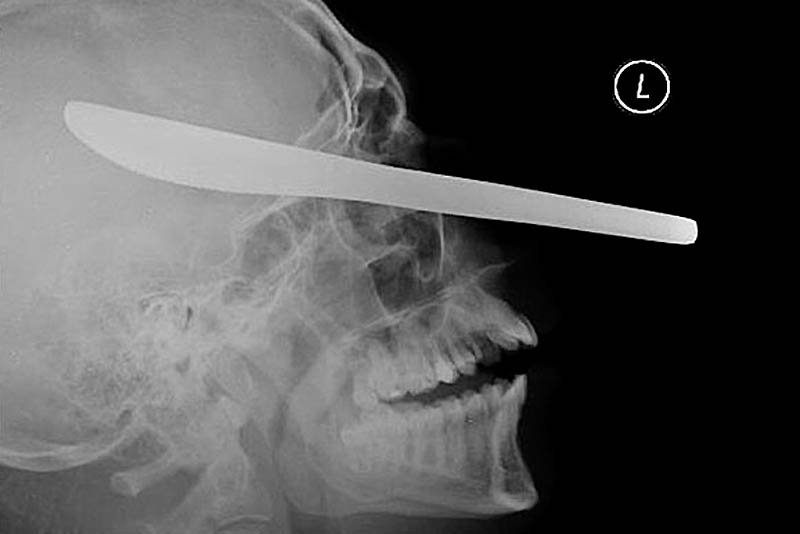

12-сантиметровый нож в черепе подростка

Нож для резки масла в глазу пациента